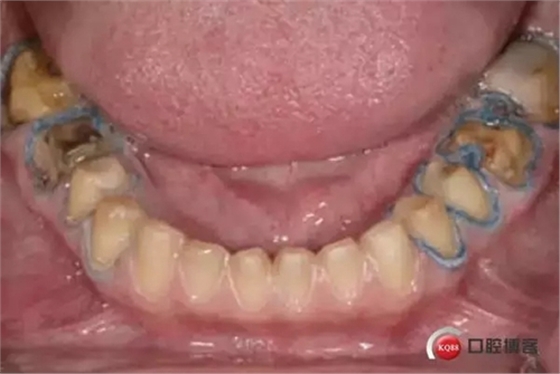

前期準(zhǔn)備:牙體預(yù)備時(shí),沿著牙齦輪廓制備牙齦緣,制備齦上肩臺(tái),盡量減少對(duì)牙齦組織的損傷。

2. 輕輕地將第一根排齦線放置在齦溝內(nèi):可以放置各種類型的排齦線(編織線或者針織線)在結(jié)合上皮附著處。排齦線型號(hào)以可以填滿1/2牙齦溝為準(zhǔn)。非浸潤(rùn)止血材料的排齦線(首選)或浸漬止血材料排齦線都可。

3. 確定基牙是否需要填充或者塑形:去除舊的修復(fù)體,評(píng)估基牙是否需要填充或者塑形。在去掉舊的修復(fù)體或者齲壞組織之前,提前進(jìn)行牙體預(yù)備。這是與院校里面的要求相反的,院校里往往要求先進(jìn)行牙體塑形或者先去除舊的修復(fù)體,然后再進(jìn)行牙體預(yù)備。

4. 完成邊緣線的制備: 第一根排齦線可以幫助保護(hù)牙齦組織不被損傷,也可幫助識(shí)別結(jié)合上皮附著處。如果制備齦下肩臺(tái),制備肩臺(tái)至第一根排齦線的冠狀面,距離上皮附著一半的距離。不要損傷牙齦。有各種各樣的器械(Zekrya 牙齦保護(hù)器 by DMG America)可用來在牙體預(yù)備的時(shí)候退縮牙齦并保護(hù)排齦線。

5. 放置第二根排齦線:選擇一根可以填滿牙齦溝的排齦線??梢杂^察到排齦線完全包繞牙體。第二根排齦線往往需要浸漬止血材料: 如果是通透性好的牙冠(二硅酸鋰)選擇氯化鋁止血材料;如果是不透明的冠(金屬冠/烤瓷冠)則選擇和硫酸鐵。注意: 盡管硫酸鐵有效,但是硫酸鐵可以使基牙染色,并可以使通透性好的牙冠透色。